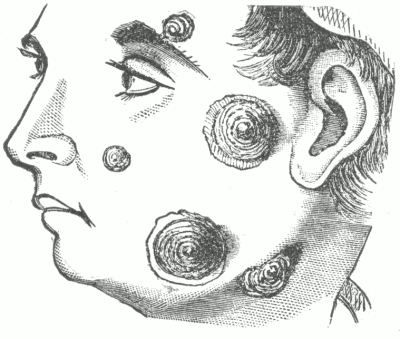

Hydrocystoma is a cystic affection of the sweat-gland ducts, seated upon the face. The lesions may be present in scant numbers or in more or less profusion. They have the appearance of boiled sago grains imbedded in the skin; the larger lesions may have a bluish color, especially about the periphery. It is not common, and is usually seen in washerwomen and laundresses, or those exposed to moist heat. In some cases it tends to disappear during the winter months. There are no subjective symptoms.